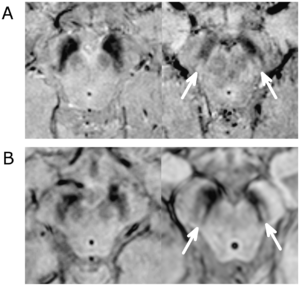

- 1.35 The Swallow Tail Appearance of the Healthy Nigrosome – A New Accurate Test of Parkinson’s Disease: A Case- Control and Retrospective Cross-Sectional MRI Study at 3T